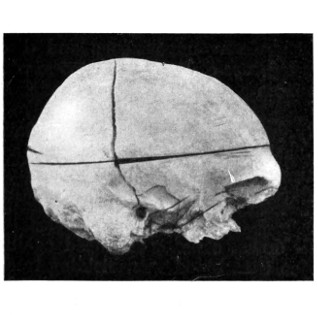

| 43 A and B. An explosive fracture of the vault of the skull | 113 |

| 44. A temperature chart illustrating the changes in temperature observed in head-injuries | 117 |